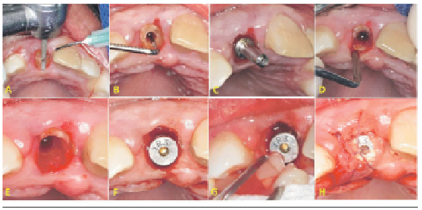

Procedimiento quirúrgico

La zona a operar se infiltró con anestesia local, lidocaína 2% más epinefrina 1:80000 (Scandicaine®, Septodont. Japon). Se diseñó una incisión sulcular a nivel palatino del incisivo central superior seguida de la reducción de la porción coronaria de la raíz (Figura 2A), luego se procedió a realizar el protocolo de fresado para la colocación de un implante dental; se inició con la fresa lanza y luego la fresa piloto. El protocolo de fresado (Kit quirúrgico Tapered®, Biohorizons. U.S.A) fue iniciado para obtener la orientación de colocación del implante dental y la cantidad de fragmento radicular a extraer (Figura 2B y 2C). Luego de las dos primeras fresas se procedió a hemisectar la raíz utilizando una fresa de fisura en dirección mesio-distal, se realizó una extracción atraumática del segmento palatino de la raíz (Figura 2D). El segmento bucal remanente fue reducido utilizando una fresa quirúrgica dejando una delgada capa de la raíz manteniendo intacta la cortical ósea vestibular (Figura 2E). Luego de extraído el fragmento radicular se procedió a realizar un tercer fresado según el protocolo para luego instalar un implante dental (Tapered Internal®, Biohorizons. U.S.A) con unas longitudes de 3,8 mm x 12 mm en el alveolo dejando 1mm de espacio entre la superficie vestibular del implante y el fragmento radicular (Figura 2F). Se dejó con la tapa de cicatrización de 3 mm de cuff. Se colocó fibrina rica en plaquetas según el protocolo Choukroun y cols.10 entre el implante dental y el fragmento radicular (Figura 2G) para luego suturar con ácido pologlicólico (Sinorgmed ®, Alemania) y puntos cruzados (Figura 2H). Se recomendó una dieta blanda luego de la cirugía de colocación de implante dental más antiinflamatorios (diclofenaco 50 mg cada 8 horas por cinco días) y antibioticoterapia (azitromicina en tabletas de 500 mg cada 24 horas por tres días; se optó por este régimen debido a su elevada concentración del fármaco en los tejidos óseos alveolares 11). No se utilizó provisionalización inmediata para no interferir con el proceso de cicatrización a nivel de la zona vestibular del implante dental colocado. La terapia antibiótica fue prescrita para reducir la carga bacteriana posoperatoria en la zona intervenida.